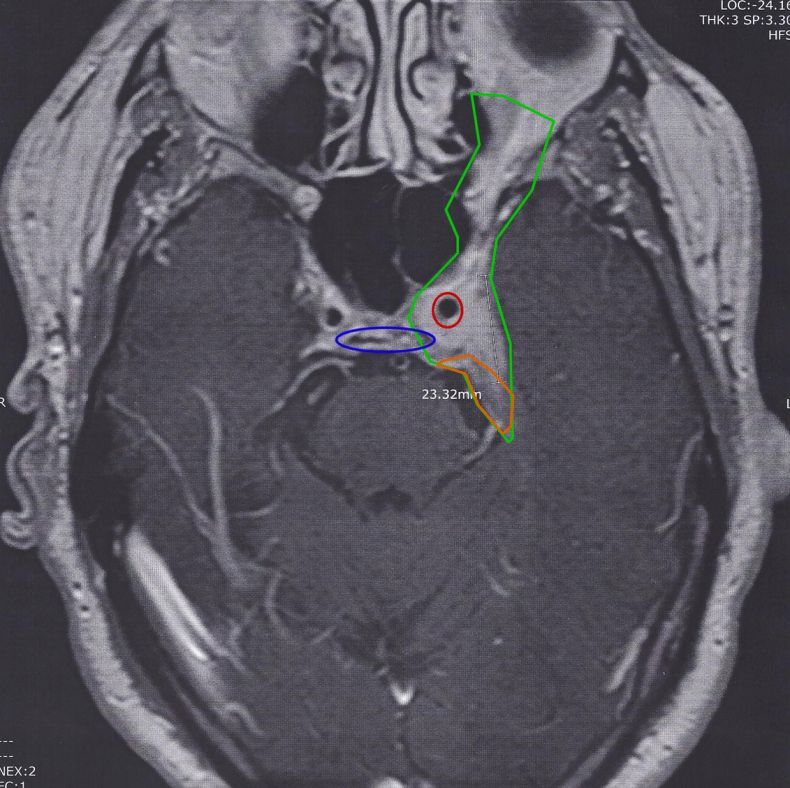

I don't want to be argumentative Sheryl, but as you know, the brain is a complex thing with each part controlling different things. This meningioma caused fainting as it had completely grown around both carotid arteries (one circled in red). The main part was inner between lobes rather than outer as is usual and the treatment included needing artery bypasses done by a team of neurosurgeons and cardiac surgeons.

Agreed this one is very atypical.

I wouldn't rule out anything other than getting all indicated tests.